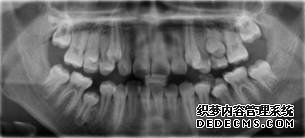

临床诊断:通过3D数字化全景机的拍片检查,患者上下牙排列拥挤,前牙受挤压向内歪斜,咬合关系异常,唇形尚可,颞下颌关节检查未见异常,无蛀牙、牙周疾病症状。经过和患者商量,选定自锁托槽矫正方案,调整牙间隙,恢复牙齿的正常排列,实现正常的咬合关系。

全景机正位片